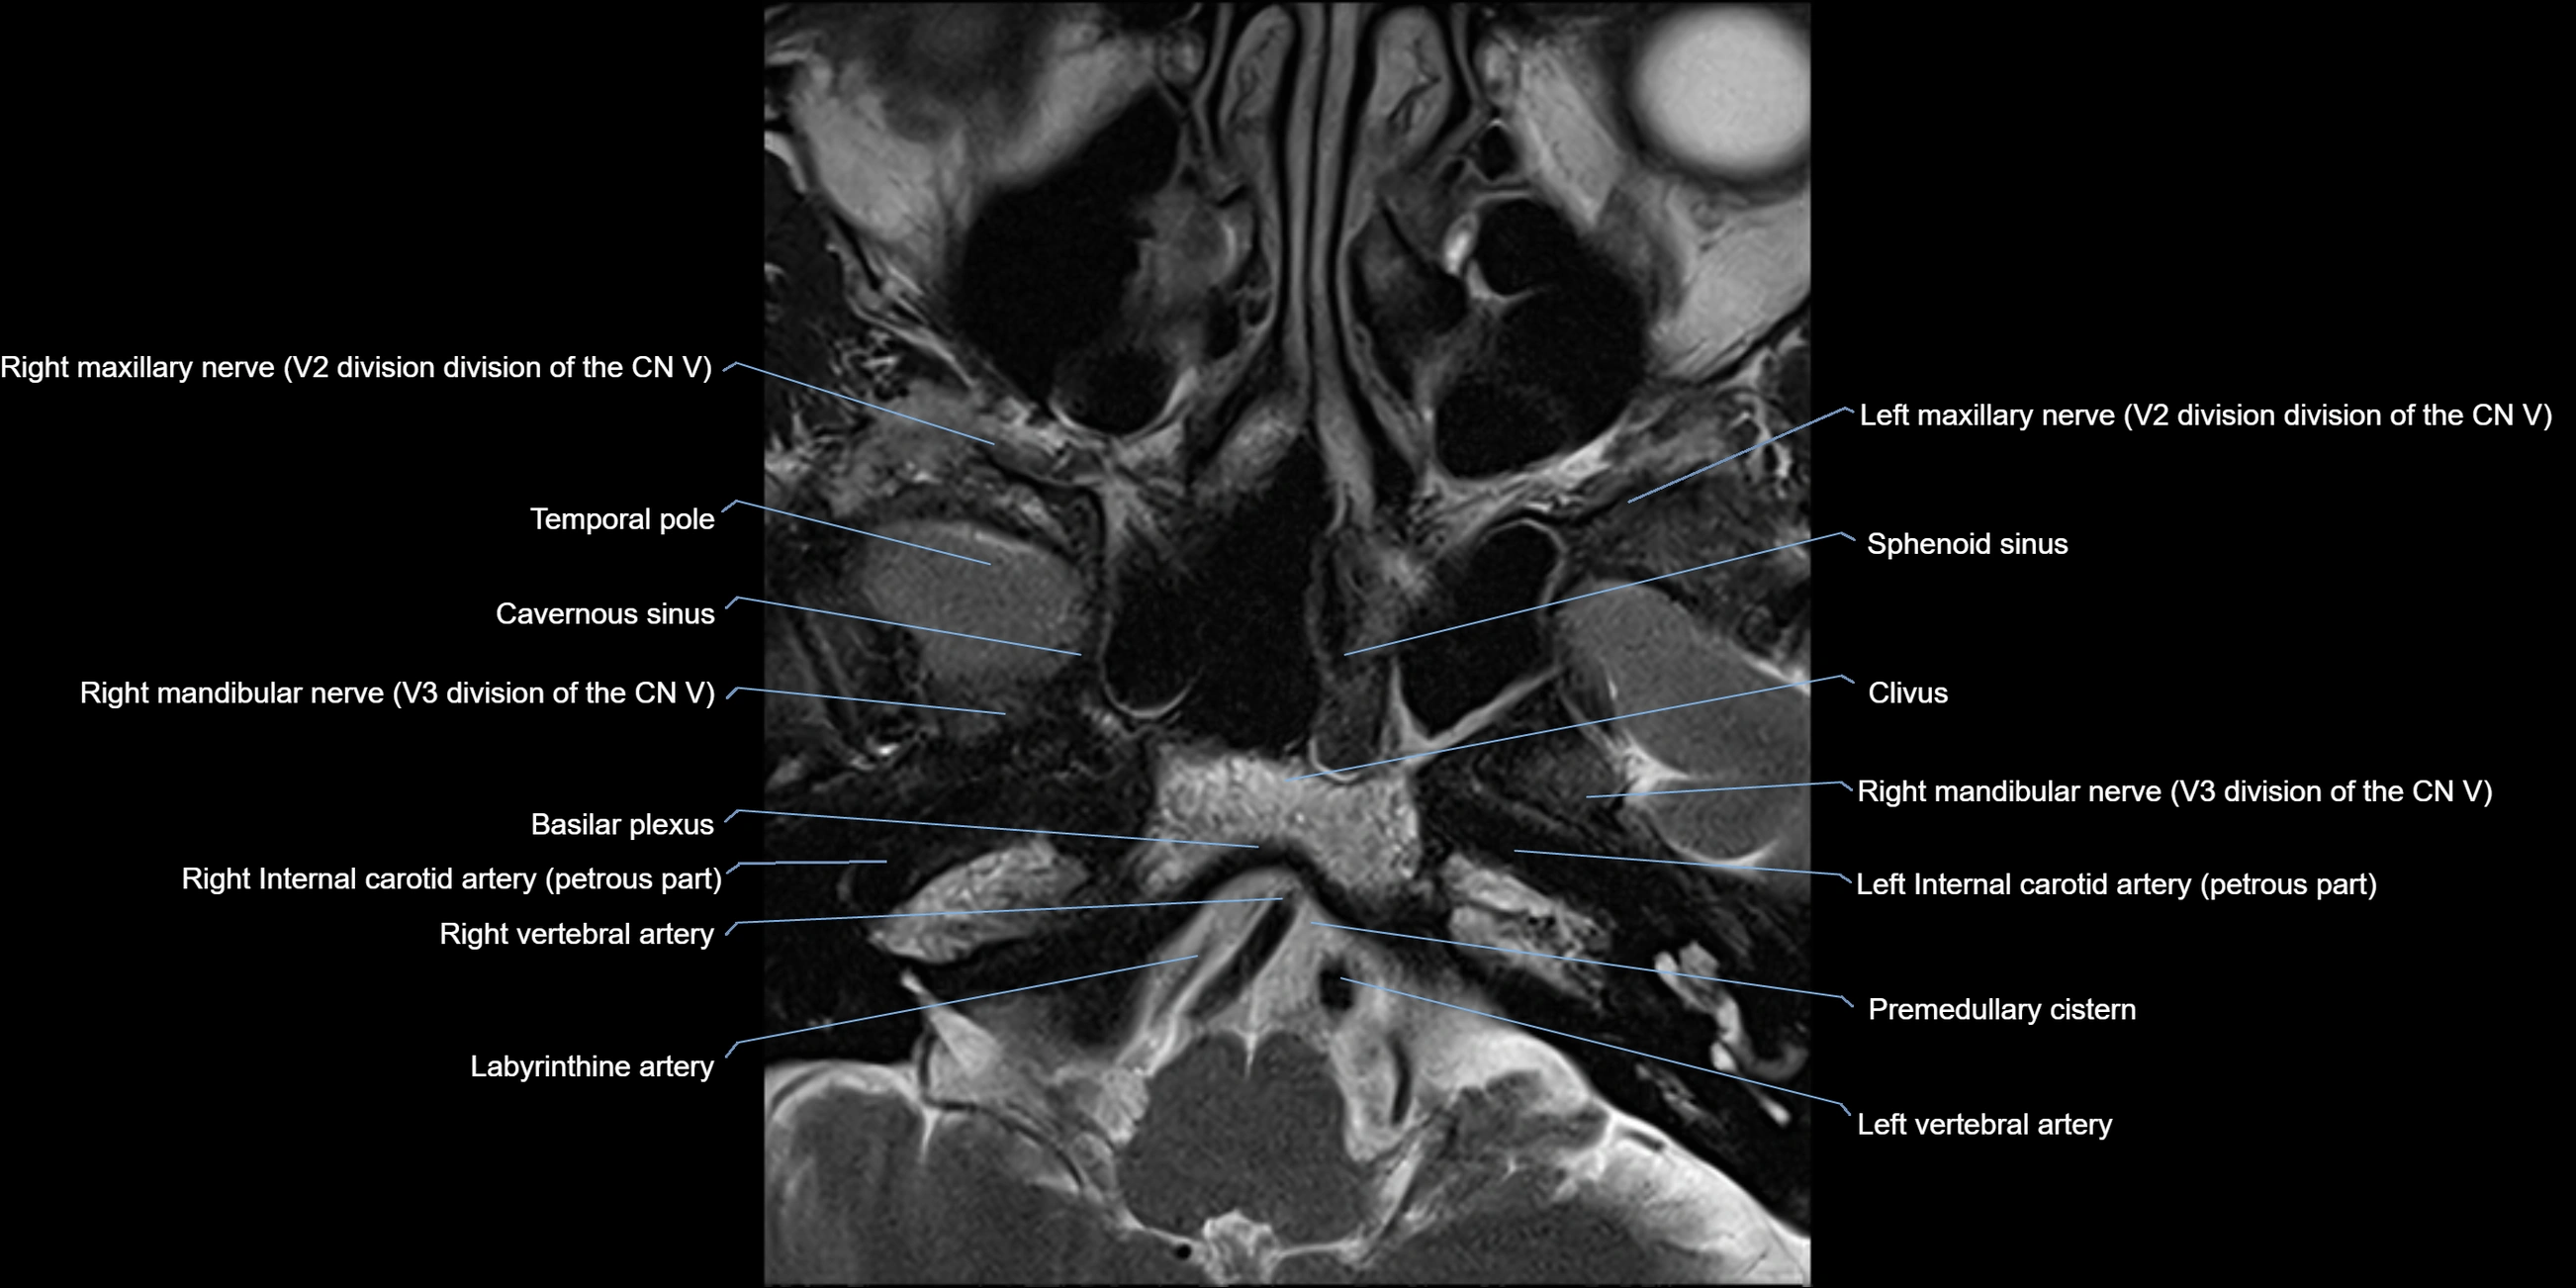

MRI Appearance

-

The abducens nerve is a small, thin, linear structure

Best visualized on high-resolution T2-weighted 3D MRI sequences (e.g., FIESTA or CISS)

Seen as a hypointense (dark) line running from the brainstem at the pontomedullary junction, traversing the prepontine cistern, and entering Dorello’s canal under the petrosphenoidal ligament, then into the cavernous sinus, and finally the orbit

May be challenging to visualize in standard MRI due to its small size

Pathology may be inferred by absence, displacement, or enhancement of the nerve

MRI images